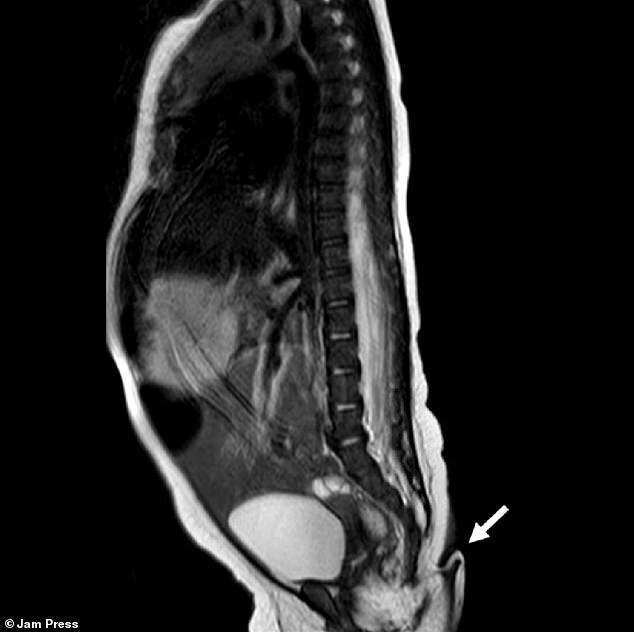

پزشکان میگویند این دختر مکزیکی از نظر سایر اندامها از جمله مغز، قلب، کلیه و حس شنوایی سالم بود. همچنین، اسکنهای پزشکی نشان داد که این دم نتیجه مشکلی در ستون مهرهها مثل دیسرافیسم نبود؛ این بیماری باعث میشود مهرهها بهدرستی شکل نگیرند و در پایین ستون آنها زائدهای شبیه دم رشد پیدا کند.

محققان پس از دو ماه دوباره این نوزاد را بررسی کردند و متوجه شدند که وزن و قد او در شرایط عادی قرار دارد. با این حال، اندازه دم 0.8 سانتیمتر بزرگتر شده بود. پزشکان درنهایت طی یک جراحی کوچک که با بیحسی موضعی انجام شد، این دم را قطع کردند. بررسیهای بیشتر روی این زائده نشان داد که دم این کودک شامل بافتهای نرم، رگ و مجموعهای از اعصاب بوده است